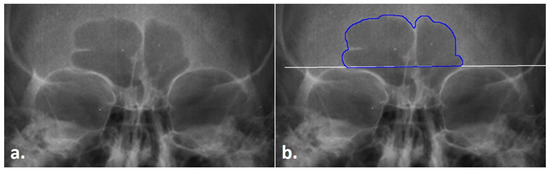

- A radiograph .tiff file with an existing sinus outline was opened in ImageJ (Figure 4a).

- Each radiograph was scaled to an orbital breadth at 39.49 mm using the line tool (Figure 4b). Specifically, the orbital breadth measurement was taken on the left orbital cavity from the dacryon to the ectoconchion. If the left orbital cavity was obscured, the measurement was taken on the right. The collection of orbital breadths differs from that of Cox et al. [16] but was necessary, as radiographic protocols can vary widely even within institutions, hindering accurate size measurements. As size is an important component of this specific technique, images were scaled using the orbital breadth (OBB) averaged from all the groups in Howell’s dataset OBB ( = 39.49 mm, s = 2.024) [32].

- The previously traced sinus outline was highlighted using the magic wand tool, and the measurement of the area (inside of the outline) and the perimeter (outer shape) was collected to obtain an overall measurement of sinus size and to serve as a secondary check that the repeated measurements of the images were scaled (Figure 4c). This measurement was recorded in the Region of Interest (ROI) Manager available in ImageJ for measurement at the end of the technique. (The ROI Manager records all objects placed on an image and enables users to review or edit the placement at any time thereafter; see the supplementary materials for details on how to implement this feature.)

- A point of origin was added at the midline of the skull using the line tool (Figure 4d). Following Cox et al. [16], this point was determined by drawing a vertical line through the skull using as many midline anatomical landmarks as possible (including nasion, anterior nasal spine, prosthion, etc.). The point of the midline that intersected the sinus baseline was determined as the origin, from which the right baseline and the 59-line lengths were collected (see steps 5 and 7).